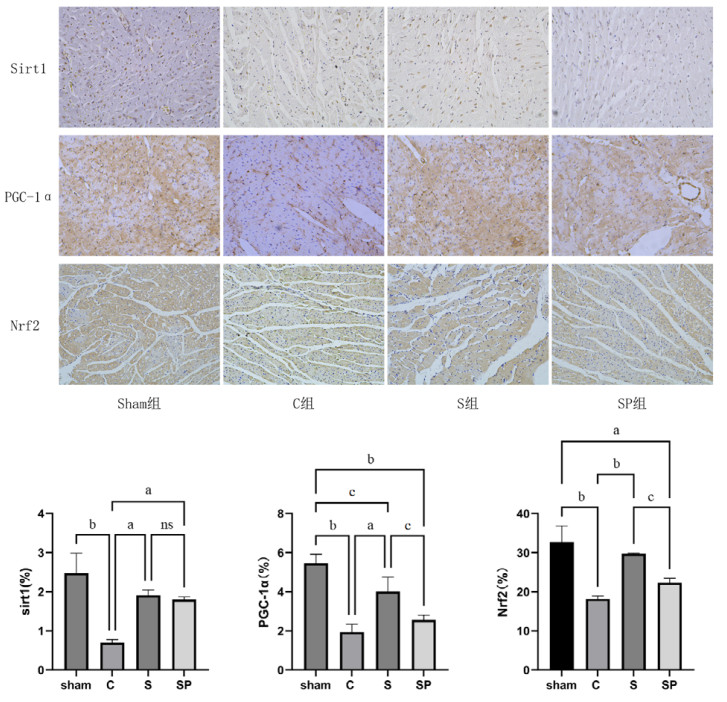

1.2.5 心肌组织免疫组织化学检查取大鼠心肌组织切片,经烤片、脱蜡,柠檬酸盐抗原修复液修复,用3%过氧化氢溶液阻断内源性过氧化物酶,封闭液封闭;加入Sirt1(1∶150)、PGC-1α(1∶250)、Nrf2(1∶200)一抗,4℃孵育过夜;第二日磷酸缓冲盐溶液洗三遍,加用HRP标记的IgG二抗,DAB显色,苏木素复染,显微镜下细胞呈棕褐色为阳性表达。计算心肌组织中Sirt1、PGC-1α、Nrf2的蛋白表达阳性率。

| 注:sham组为假手术组,C组为CLP模型组,S组为CLP+Sirt1激动剂组,SP组为CLP+Sirt1激动剂组+PGC-1α抑制剂组;a为P < 0.01,b为P < 0.001,c为P < 0.05,ns为差异无统计学意义 图 4 各组心肌组织中免疫组织化学图(DAB染色,Sirt1、PGC-1α×400,Nrf2 ×200) Fig 4 Immunohistochemistry in myocardial tissues of each group (DAB staining, Sirt1、PGC-1α ×400, Nrf2 ×200) |

C组的Sirt1、PGC-1α、Nrf2蛋白表达量较sham组低(P < 0.05),S组的大鼠Sirt1、PGC-1α、Nrf2蛋白表达高于C组(P < 0.05),而SP组大鼠与S组大鼠Sirt1表达无明显改变,但PGC-1α和Nrf2的表达量较S组均低(P < 0.05)。